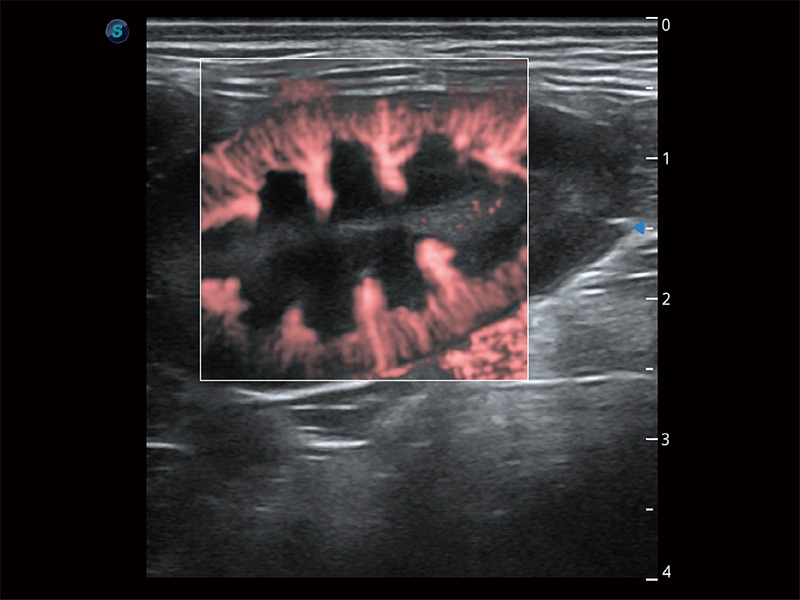

在传统二维血流成像的基础上,呈现血流的立体感,具有动感的生命力之美。即便是微小的血管也能轻松应对,提高了血流的视觉敏感性。